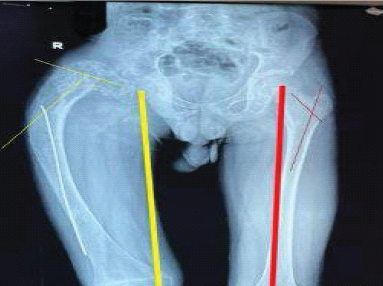

Repeated Surgeries and Clinical Assessment Using 3D Gait Analysis in Unilateral Congenital Short Femur: A Case Report

Hiroki Fujita , Yutaka Kozakai , Misa Kaga , Junya Shimizu , Atsushi Teramoto